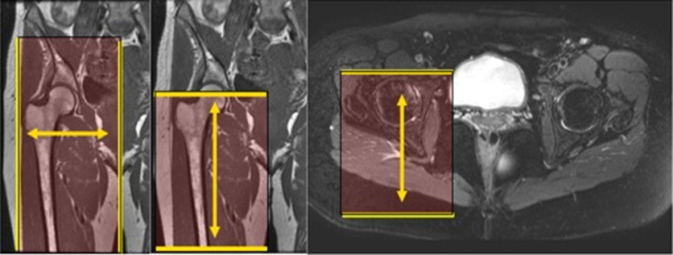

| AXIAL | T1 | TSE | 3mm | 1mm | COVER AREA AS SHOWN BELOW. FOV = Mid hip joint through mid thigh. Slices to cover entire SI Joints to lesser trochanters. | Unilateral | |

| AXIAL | T2 SPAIR | TSE | 3mm | 1mm | SPAIR | COVER AREA AS SHOWN BELOW. FOV = Mid hip joint through mid thigh. Slices to cover entire SI Joints to lesser trochanters. | Unilateral |

| COR | T1 | TSE | 3mm | 1mm | COVER AREA AS SHOWN BELOW. FOV = Sacrum thorough femoral head. Increase slices to cover skin to skin A to P. | Unilateral | |

| COR | STIR (TE=50-60) | TSE | 3mm | 1mm | COVER AREA AS SHOWN BELOW. FOV = Sacrum thorough femoral head. Increase slices to cover skin to skin A to P. | Unilateral | |

| SAG Unilat | T2 SPAIR | TSE | 3mm | 1m | SPAIR | COVER AREA AS SHOWN BELOW. FOV= Iliac crests through lesser trochanters. Slices to cover midline through greater trochanter. | Unilateral |